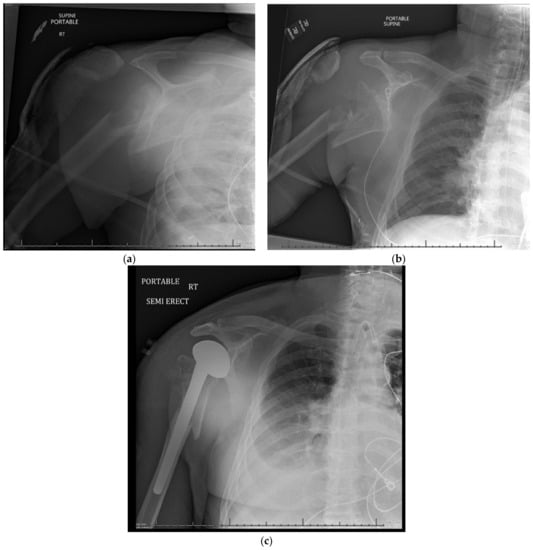

15. Hemiarthroplasty

15.1. Patient Positioning

15.2. Surgical Approach

15.3. Postoperative Management